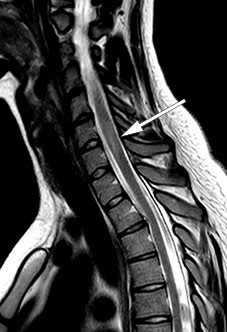

MR caput og MR totalmedulla viste høysignalforandringer i mer enn 50 % av medullas diameter med svak kontrastoppladning ved nivåene C4–C5, C6–C7 og Th11–Th12 (figur 1), men tilbakegang av meningittforandringene. Radiologen mente bildene var best forenlig med akutt disseminert encefalomyelitt. Ny lumbalpunksjon (tabell 1) viste økende celletall og moderat økt totalprotein og albumin forenlig med blod–hjernebarrieresvikt. På bakgrunn av økende celletall i cerebrospinalvæsken ble det igjen gitt aciklovir inntil negativ PCR for herpes simplex-virus forelå.

Kontroll-MR en måned senere viste tilkommet lesjon i høyre thalamus uten kontrastoppladning (figur 2) samt to nye, små lesjoner med kontrastladning i medulla ved C5, C6 og muligens også Th5. De infratentorielle lesjonene hadde gått fullstendig tilbake, og forandringene i medulla oblongata var redusert.

Etter utskrivelse viste det seg at den andre anti-MOG-prøven fra serum var positiv. Mot slutten av nedtrappingen av prednisolon hadde pasienten to korte innleggelser i medisinsk avdeling på grunn av vedvarende hodepine og urinveisinfeksjon. MR av hjerne og ryggmarg og nevrologiske undersøkelser viste da ikke noe nytt. Rett etter avsluttet prednisolonkur ble pasienten innlagt på nevrologisk avdeling med økende synsproblemer, diplopi, nystagmus mot høyre og parese for abduksjon av høyre øye. MR 20 dager etter forrige undersøkelse og nesten to måneder etter oppstart med rituksimab viste tilkomne lesjoner subkortikalt frontalt bilateralt, i medulla, i venstre lillehjernepedunkel samt i corpus callosum (figur 4). Lumbalpunksjon viste fortsatt moderat pleocytose (tabell 1, siste kolonne). Pasienten fikk som tidligere metylprednisolon med god effekt, og ble deretter skrevet ut til hjemmet med langvarig nedtrapping av prednisolon og snarlig kontroll på poliklinikken.